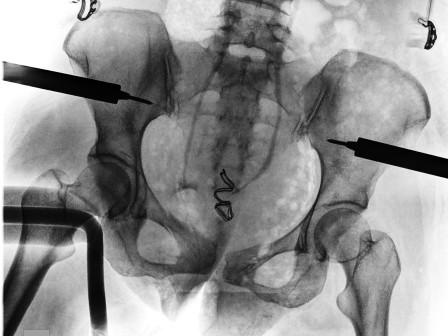

hématome profond sur fracture du bassin, refoulant la vessie

scanner cas précédent

fracture du bassin, ceinture pelvienne en place

pelvic clamp sur une radiographie pour fracture du bassin et embolisation

Le conditionnement et la réanimation sont fondamentaux pour le patient en choc hémorragique mais le traitement définitif à mettre en place le plus rapidement possible est souvent une intervention chirurgicale. L’hémostase chirurgicale est parfois obtenue de manière temporaire par immobilisation des foyers de fracture (fixateur externe, pelvic clamp) plutôt que par des solutions d’ostéosynthèse définitive.

Certaines situations peuvent faire recourir aux embolisations artérielles en radiologie interventionnelle, en traumatologie pour les fractures du bassin par exemple.